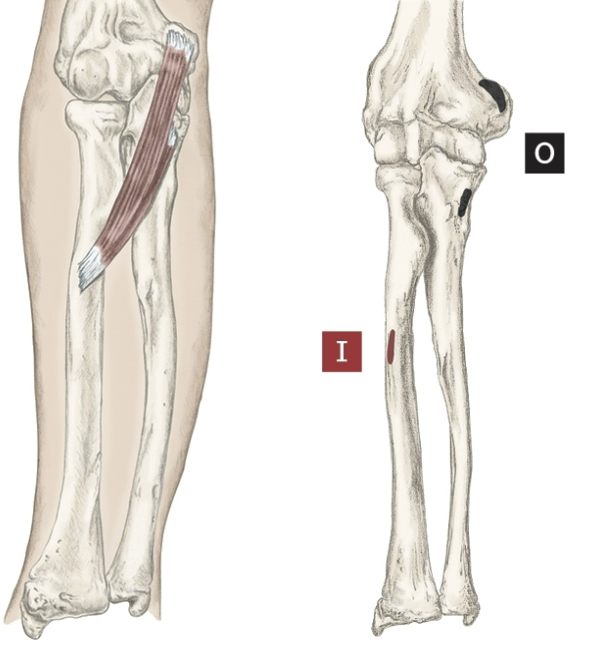

Action of Flexor Digitorum Profundus

Flexion of 2-5 fingers [ MCP,PIP,DIP]

Origin of Flexor Digitorum Profundus

Proximal ulna and anterior, and medial

Insertion of Flexor Digitorum Profundus

Base of palmar surface of distal phalanges 2-5

Nerve that the Flexor Digitorum Profundus innervates

Median Nerve